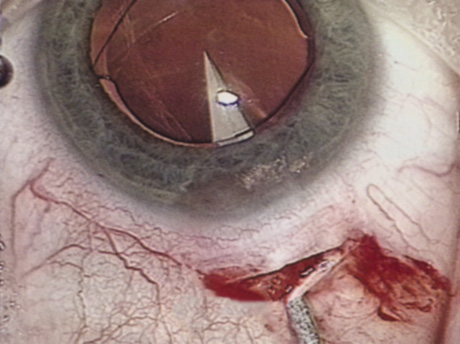

ANTERIOR CAPSULOTOMY

One of the most beneficial techniques developed over the last decade is capsulorrhexis. A continuous curvilinear anterior capsular opening helps prevent intraoperative and postoperative complications. With capsulorrhexis, mechanical strength of the capsular opening is superior to that in a can-opener capsulotomy; thus, a tear to the posterior capsule with subsequent vitreous loss is much less likely.96 Capsulorrhexis allows for nuclear manipulation with less risk of posterior capsule rupture. Cortex removal is made easier as well, because it becomes easier to differentiate cortical material from anterior capsule. Should a posterior capsular tear occur, sulcus fixation is more likely attainable with the presence of a clearly visible residual anterior capsular rim. Placement of both IOL haptics into the capsular bag is more certain with capsulorrhexis because the surgeon can more easily visualize the haptics gliding beneath the anterior capsular rim.

Capsulorrhexis can be performed with a cystitome, capsulorrhexis forceps, or combination-type instruments. Regardless of which instrument is used, several principles can help the surgeon successfully complete capsulorrhexis. It is important to maintain the anterior chamber, because making the chamber shallow increases tension on the zonules and causes the tear to run peripherally. The authors recommend the use of a viscoelastic agent for maintaining chamber depth and, of course, for endothelial protection. Therefore, if the tear begins to run peripherally, the surgeon should redeepen the anterior chamber before attempting to redirect the tear. Additionally, folding the capsule margin can aid the surgeon in redirecting the tear more accurately (Fig. 10).

Fig. 10. The capsulorrhexis tear is more easily redirected by folding the capsule over, in advance of the tear.